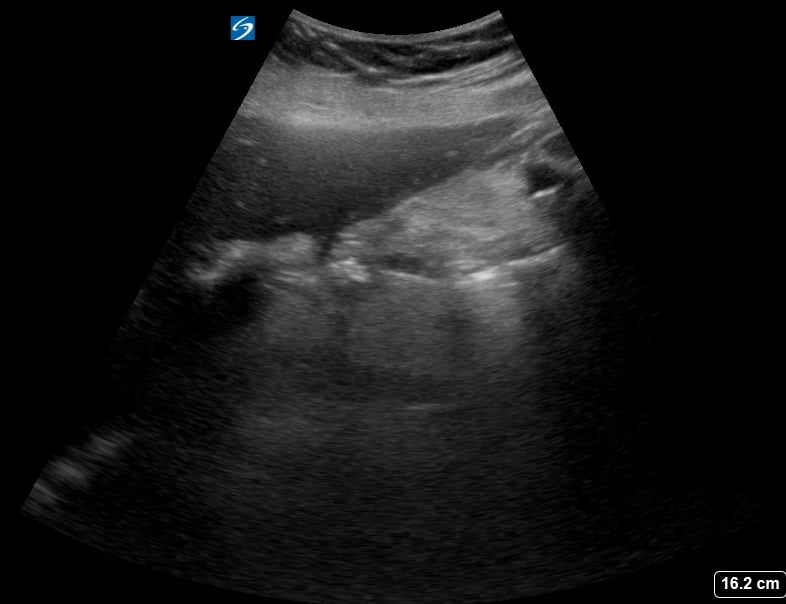

Gallstones are hardened deposits of digestive fluid that can form in the gallbladder, a small organ beneath the liver. In abdominal ultrasound, these concretions appear as hyperechoic structures within the gallbladder lumen, often with posterior acoustic shadowing. Their presence is a common finding during abdominal scans, frequently associated with symptoms like right upper quadrant pain, nausea, and vomiting, particularly after fatty meals.

Medical ultrasound plays a crucial role in diagnosing gallstones and related conditions such as cholecystitis (gallbladder inflammation) or choledocholithiasis (gallstones in the bile duct). Sonographic evaluation helps assess their size, number, and mobility, guiding clinical management and treatment decisions for patients experiencing abdominal discomfort or suspected biliary tract pathology.